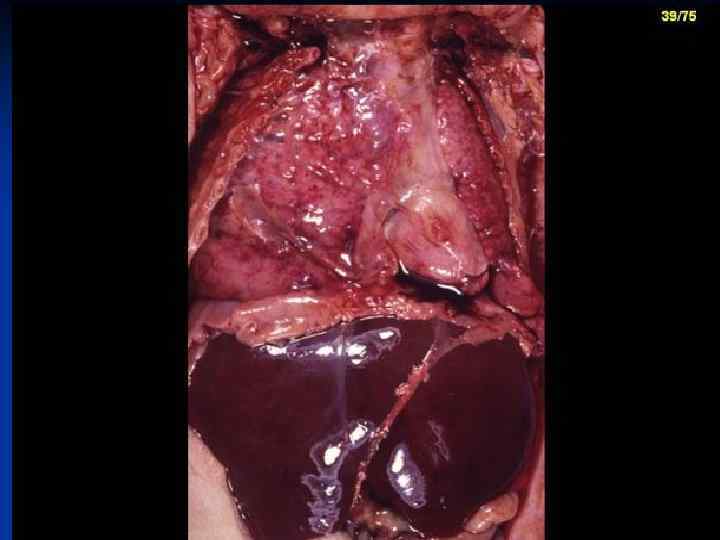

Pathomorphological Stage of HMD The lungs don’t smooth out, primary atelectasis, engorgement of vessels n Diffuse edema of pulmonary tissue with hemorrhage to connective tissue & parenchyma n The lungs are without air, with condensation, lung appear “liver-like” n

Secondary PPH due to congenital pneumonia